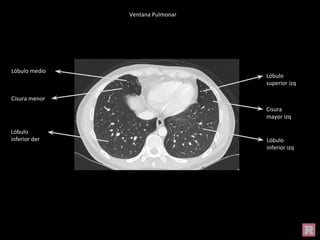

Ventana Pulmonar

Lóbulo

inferior izq

superior der

superior izq

Cisura

mayor izq

inferior der

Cisura menor

mayor der

Lóbulo medio